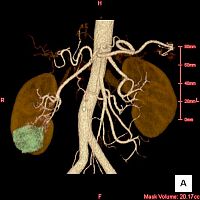

検査結果の画像を左欄に示します(マウスを重ねると拡大します)。

画像を見た結果は十中八九 癌であるということでしたが、なぜ十中八九なのかは説明はありませんでした。

さて慶應義塾大学病院でも2011年1月7日(金)に改めてCT検査を行い、2011年1月14日(金)に診察を受けました。 CT検査はやはり単純CTとヨード製剤を使用した造影CTです。 CTで計測された腫瘍の大きさは35mmでした。 さらに検査結果は以下のような観点で診断されます。

このようにして診断が下された私の検査結果は、ほぼ間違いなく癌であり病期分類は T1a N0 M0 のステージT期ということでした。